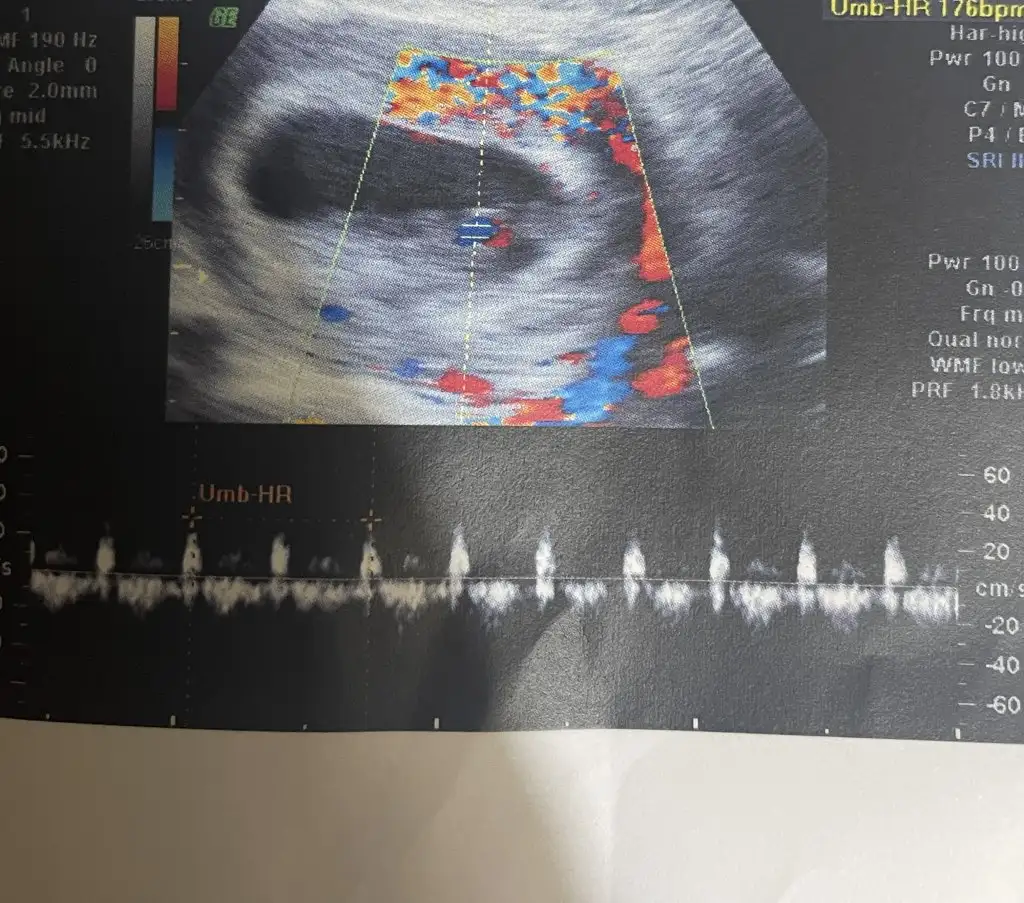

1ciftyesilgozz merhaba kizlar 8 haftalik olduk dun doktora gittik iki oglumdan sonra fikirlerinizi alayim varmi bizede bir tahmin

Eklentiler

• ED29E629-549D-4E18-9554-8B8E59BB173E.webp

16 KB · Görüntüleme: 70

• 2EB25C88-F3C3-4BF4-A081-754B702961A4.webp

94,6 KB · Görüntüleme: 56

• 76529EE5-2145-4C63-8B1D-C3103B91523A.webp

106,6 KB · Görüntüleme: 56